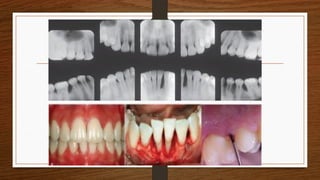

• Two gingival tissue responses can be found:

• 1. Severe, acutely inflamed tissue, often proliferating, ulcerated and fiery red. Bleeding may

occur spontaneously or on slight stimulation

• 2. Gingival tissue may appear pink, free of inflammation and occasionally with some degree

of stippling, although the last feature may be absent

• Despite the apparently mild clinical gingival appearance, deep pockets can be demonstrated

by probing

• Two gingivaltissue responses can be found: • 1. Severe, acutely inflamed tissue, often proliferating, ulcerated and fiery red. Bleeding may occur spontaneously or on slight stimulation • 2. Gingival tissue may appear pink, free of inflammation and occasionally with some degree of stippling, although the last feature may be absent

• Despite theapparently mild clinical gingival appearance, deep pockets can be demonstrated by probing • Systemic manifestations such as weight loss, mental depression and general malaise. • Generalized aggressive periodontitis patients must have their medical histories updated and reviewed.